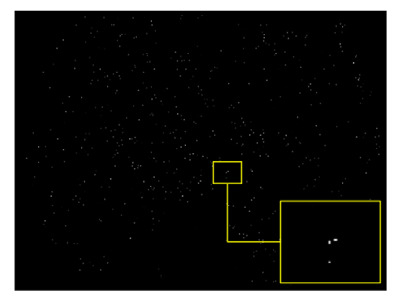

2.2. Data Pre-Processing

2.3. Patch Generation